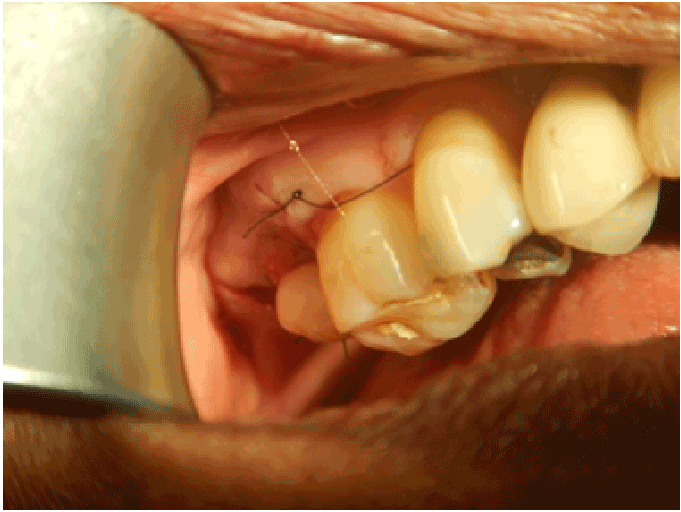

图4:在手术当天发布临时基台和冠的颊面视图(种植体放置),调整皮瓣并用尼龙线缝合

图5:在手术当天发布临时基台和冠腭侧视图(种植体放置),调整皮瓣并用尼龙线缝合。